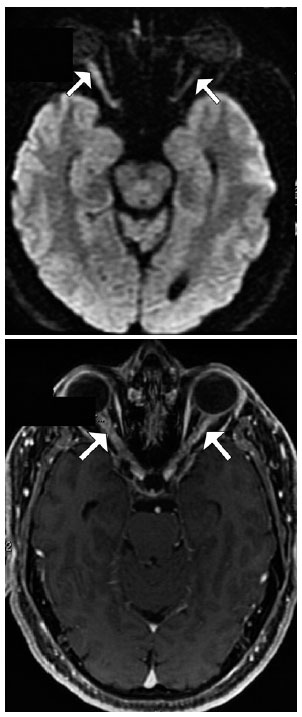

T2-weighted MRI revealed hyperintense thickening in both optic nerves that was associated with post-contrast enhancement and mild diffusion restriction, which suggested concomitant inflammatory and ischemic processes in both eyes (Figure 4).

For patients with double seronegative NMOSD, further research is needed to better elucidate the clinical and immunopathological features and to define whether AON should be considered as part of NMOSD. The finding of diffusion restriction on MRI suggests that visual loss was associated with ischemic injury and supports the notion of a mixed mechanism of inflammation and ischemia in AON(11). However, we think that the presence of diffusion restriction on MRI helps to differentiate demyelinating optic neuritis from other inflammatory optic neuropathies such as NMO and AON.